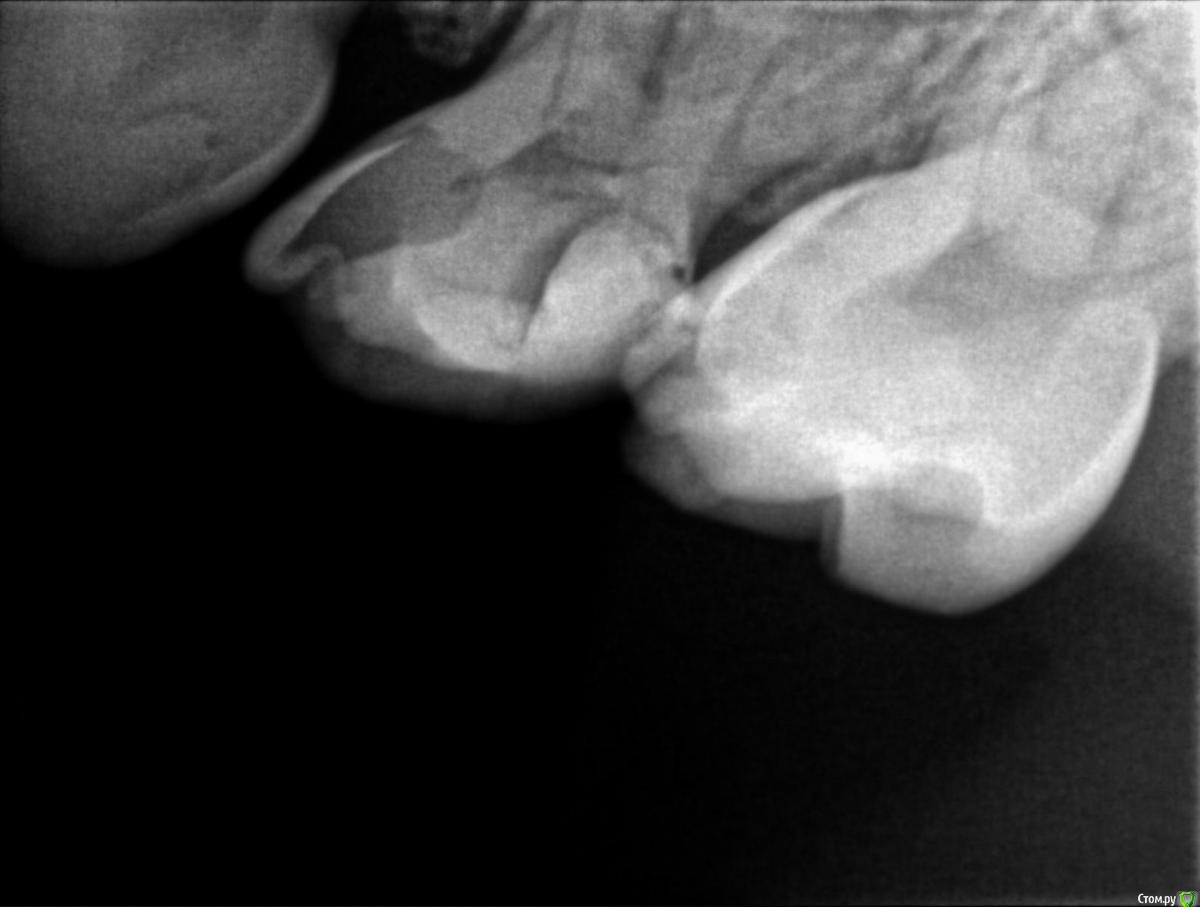

Пошли к врачу, сделали рентген и на рентгене видно что начал образовываться кариес почти на всех молярах, либо под пломбами, либо на стыке зубов. Так как зубы уже леченые доктор говорит что лечить дальше смысла нет, пломба держаться не будет, выпадет снова, предлагают ставить коронки сразу на все моляры, а зуб где уже большая пломба (зуб I на ренгене) просто удалить (не болит) и поставить space mantainer + удалить зуб А.

На наш НЕпрофессиональный взгляд, пломбы не такие уж большие чтоб закатывать в коронки, у старшего сына была аналогичная вообщем то ситуация и когда были в россии да, пломбы вываливались, на их место ставили новые, иногда удаляли нерв, но в итоге до смены зубов все дошло без удаления.

На всякий случае прикрепляю снимки, буду рад услышать мнение.